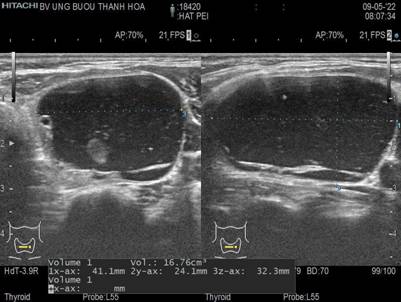

* Dưới đây là trường hợp bệnh nhân được điều trị nang tuyến giáp bằng phương pháp chọc hút và tiêm cồn:

(Ảnh: Bệnh nhân trước khi điều trị)

(Ảnh: Siêu âm nang giáp chảy máu thùy giáp trái kích thước lớn)

Nang giáp có biến chứng chảy máu trong nang thường làm cho nang giáp tăng kích thước nhanh chóng kèm cảm giác đau, khó chịu nhiều ở vùng cổ. PEI là phương pháp đơn giản, hữu hiệu được lựa chọn cho bệnh nhân này.